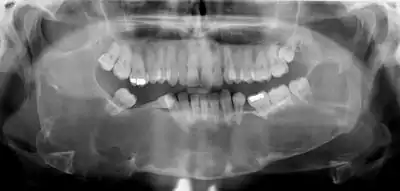

Large odontogenic keratocyst with impacted wisdom teeth superficial to lesion

Diagnosis is usually radiological. However, definitive diagnosis is through biopsy. Aspirational biopsy of odontogenic keratocysts contains a greasy fluid which is pale in colour and contains keratotic squames.[11][2] Protein content of cyst fluid below 4g% is diagnostic of odontogenic keratocysts.[2] Smaller and unilocular lesions resembling other types of cysts may require a biopsy to confirm the diagnosis.[9] On a CT scan, the radiodensity of a keratocystic odontogenic tumour is about 30 Hounsfield units, which is about the same as ameloblastomas. However, ameloblastomas show more bone expansion and seldom show high density areas.[12]

Radiographs of odontogenic keratocysts show well-defined radiolucent areas with rounded or scalloped margins which are well demarcated.[11] These areas can be multilocular or unilocular. The growth pattern of the lesion is very characteristic from which a diagnosis can be made as there is growth and spread both forward and backward along the medullary cavity with little expansion. No resorption of teeth or inferior dental canal and minimal displacement of teeth is seen. Due to lack of expansion of the odontogenic keratocyst, the lesion can be very large when radiographically discovered.[9]